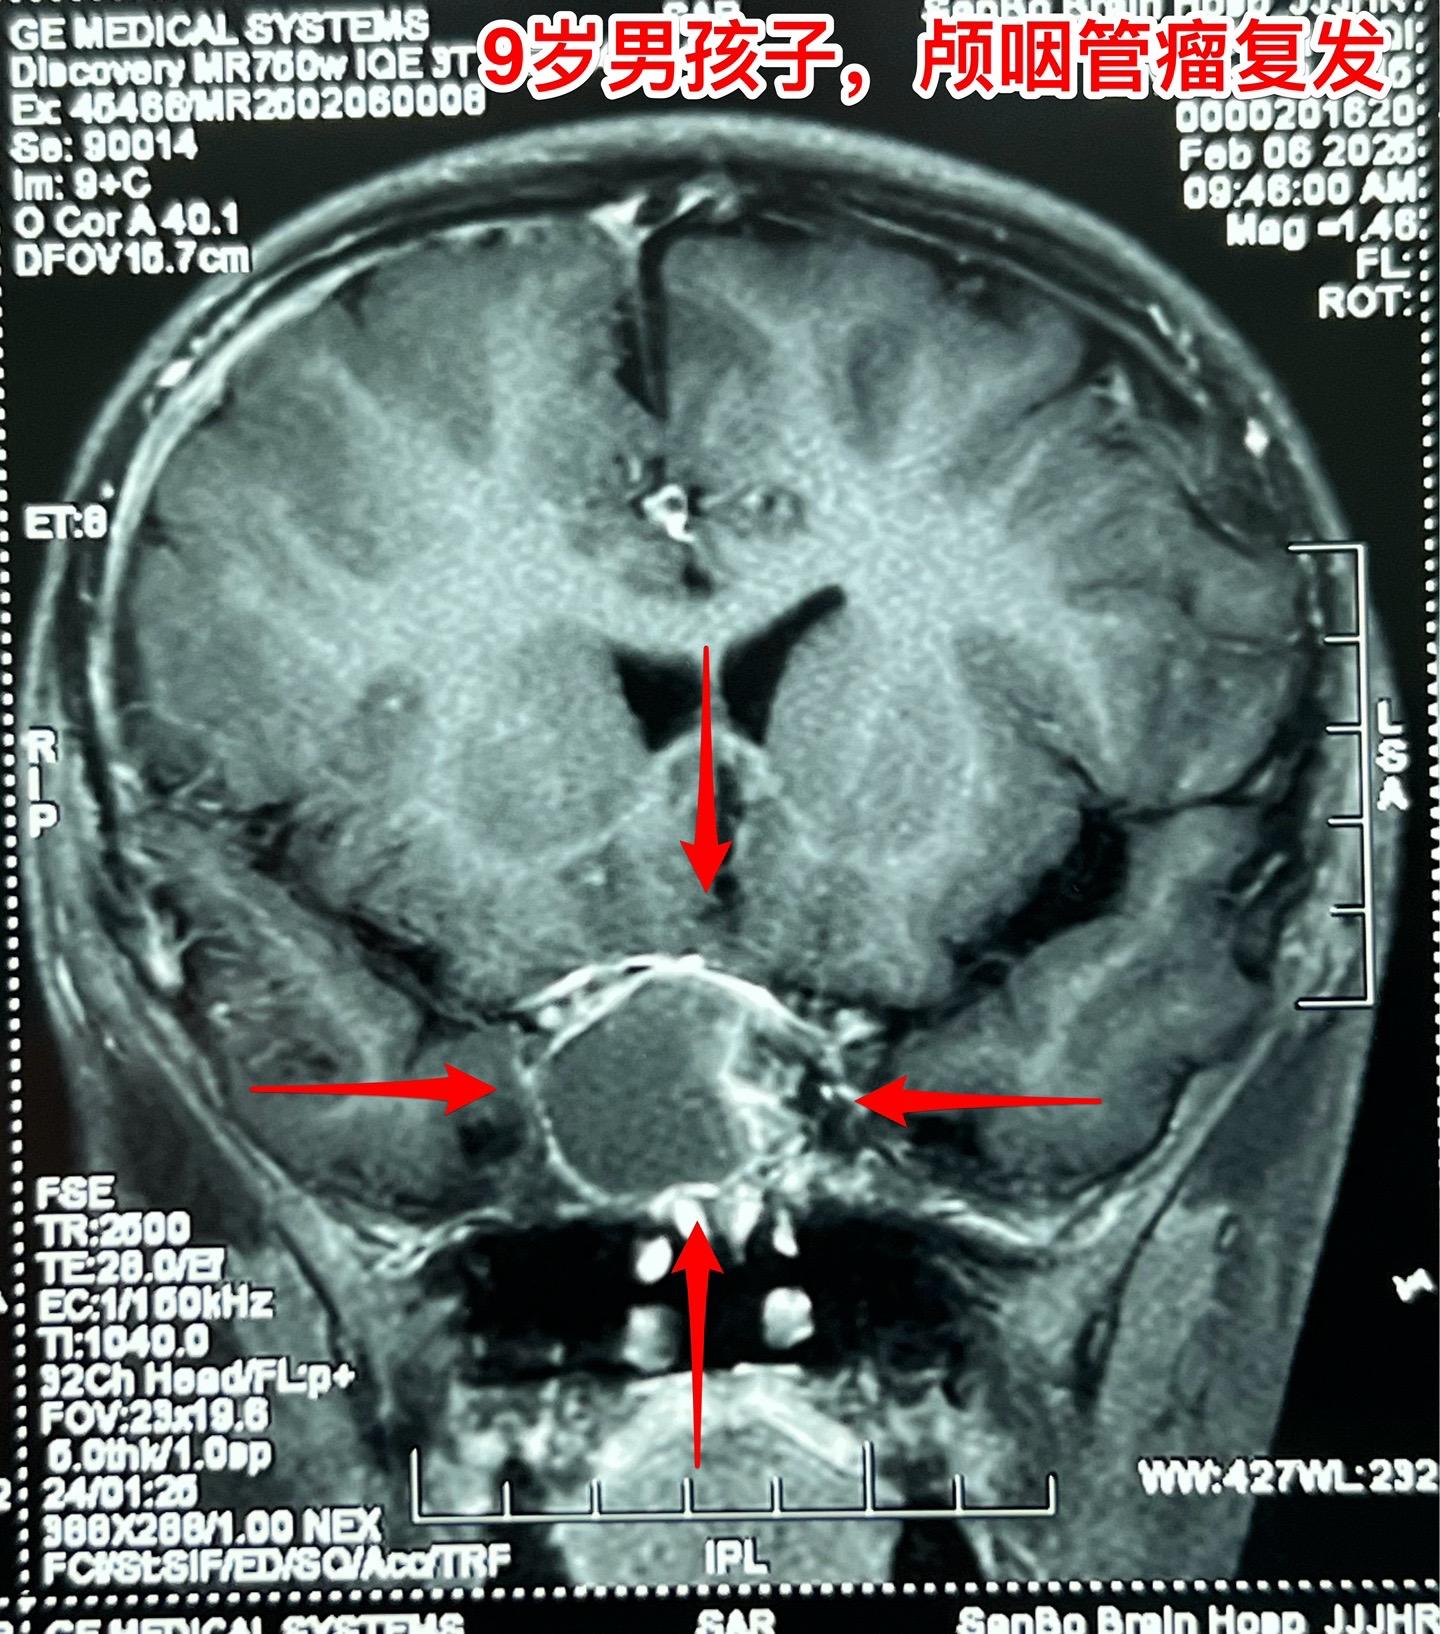

九岁男孩子颅咽管瘤复发,肿瘤生长快。南阳市男孩子2年半前曾经作了一次手术,2024年2月复查磁共振显示垂体窝内无肿瘤复发,鞍背骨质内有可疑异常信号。2025年1月复查磁共振即显示肿瘤复发而且直径达4厘米,患儿家长不敢相信肿瘤居然长得这么快!正月初八患儿即来住院,复查磁共振及CT见图。 病友们经常咨询的问题是肿瘤的生长速度。虽然颅咽管瘤是良性肿瘤,但是不能肯定地说颅咽管瘤的生长速度就很慢。即使在较长时间内肿瘤生长缓慢,也可能在某个时间段出现快速生长,也就是说颅咽管瘤的生长速度不是匀速的,难以预